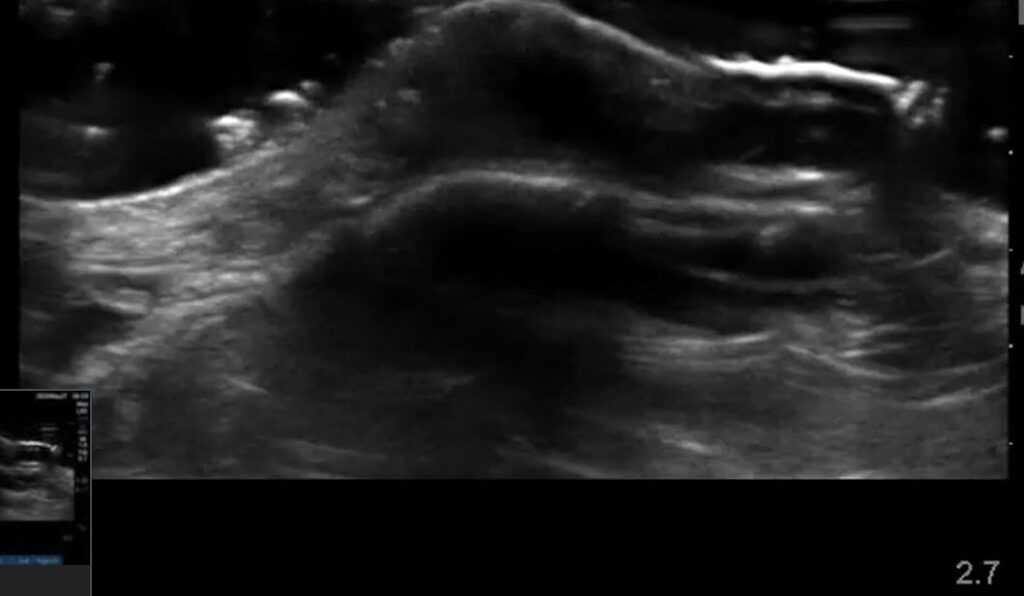

Diagnosing bursitis medically often involves clinical examination and imaging. Ultrasound is a valuable tool in its diagnosis and management, allowing for clear visualization of the inflamed bursa, its fluid content, and surrounding tissue changes. This helps differentiate bursitis from other conditions, guiding effective treatment strategies.